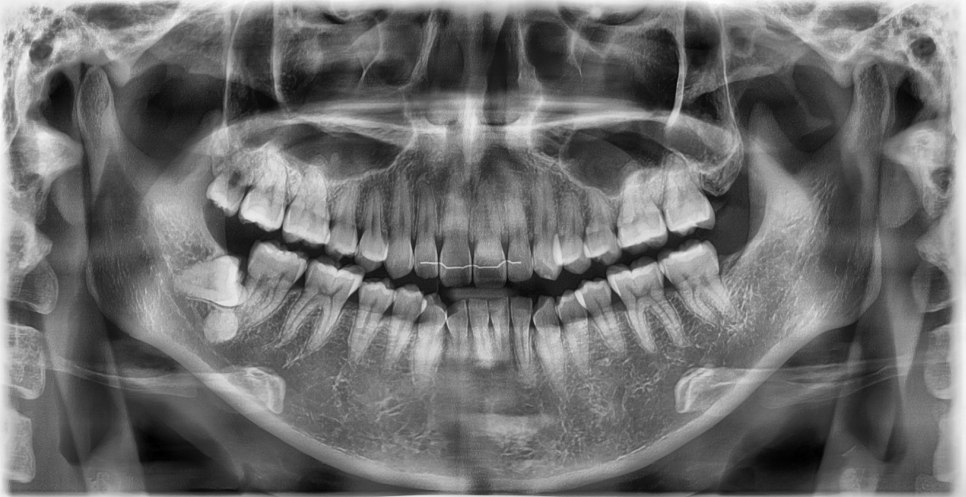

(우리 데스크 선생님 파노라마 사진입니다 ㅎㅎ)

사실 치아는 속까지 다 들여다볼 수 있는 구조가 아니다 보니

육안으로는 문제가 없어 보여도

X-ray를 찍어보면 예상 못 했던 부분이 보일 때가 많습니다.

특히 뿌리 쪽 염증이라든가, 겉으로는 보이지 않는 충치나

잇몸 뼈의 변화 같은 건

눈으로만 봐서는 절대 알 수가 없습니다.